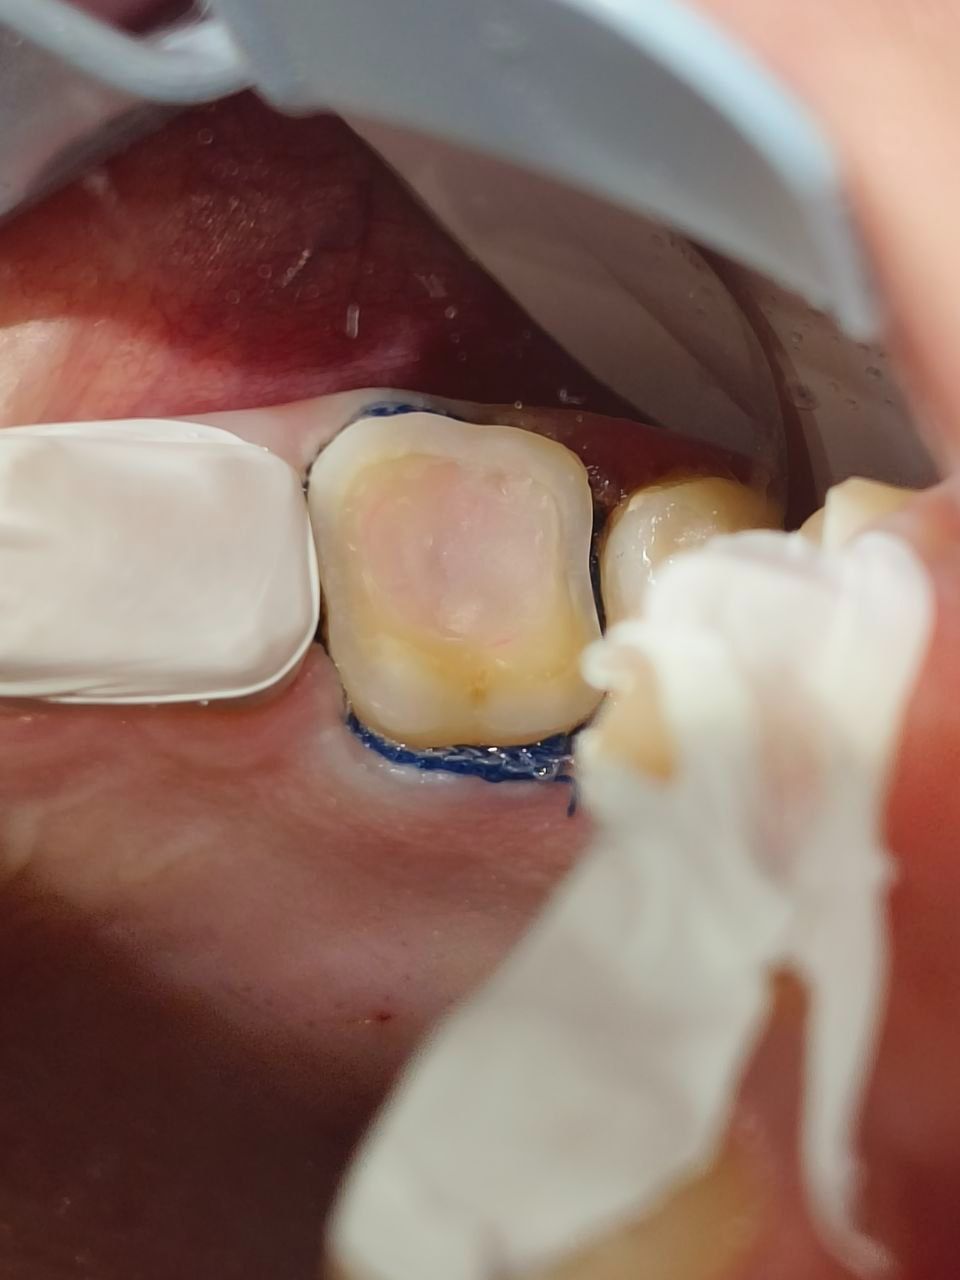

Накладка винир

Существуют конструкции, которые представляют собой комбинацию винира и накладки на зуб, закрывающие не только переднюю лицевую поверхность, но и жевательную поверхность зуба. Эти структуры могут быть названы винирами на 360 градусов, винирлеями или полукоронками.

Такие конструкции обычно используются в случаях, когда необходимо восстановить не только эстетику зуба, но и его функциональные характеристики, особенно на жевательных поверхностях. Это может быть полезно при восстановлении зубов с обширными повреждениями, кариесом или стиранием.